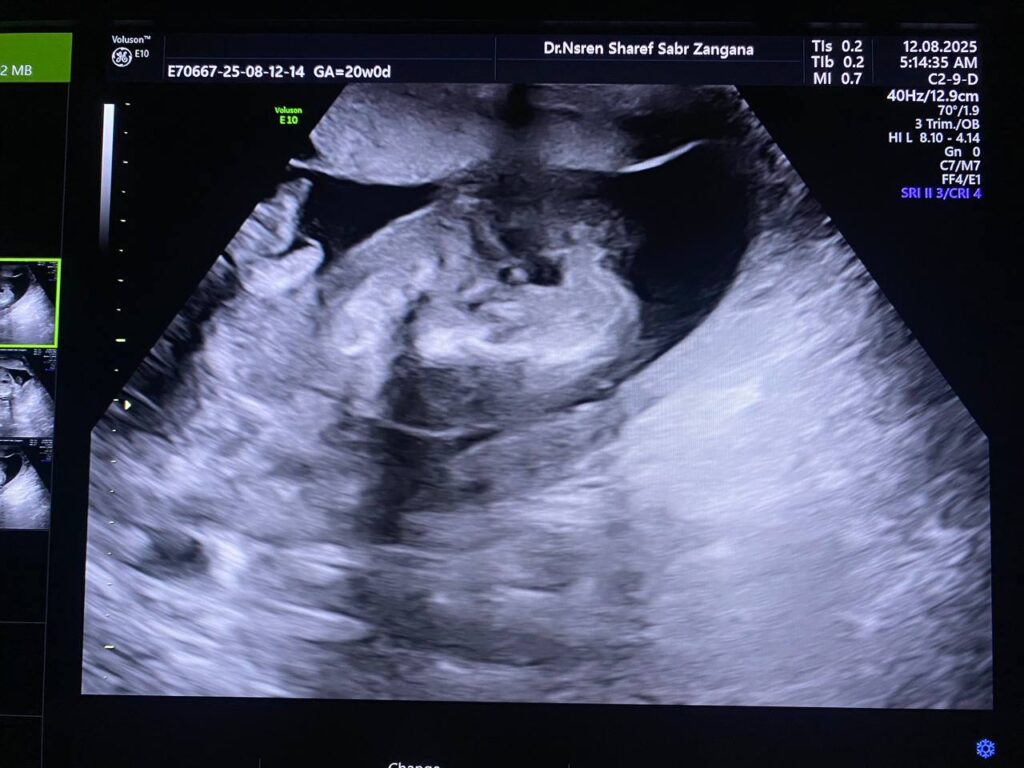

Multiple congenital anomaly seen , small chest , curve long bones , short limbs , kyphoscoliosis, congenital heart disease , edematous skin, picture mostly of thanatophoric dysplasia

F.L. = 16w+2d